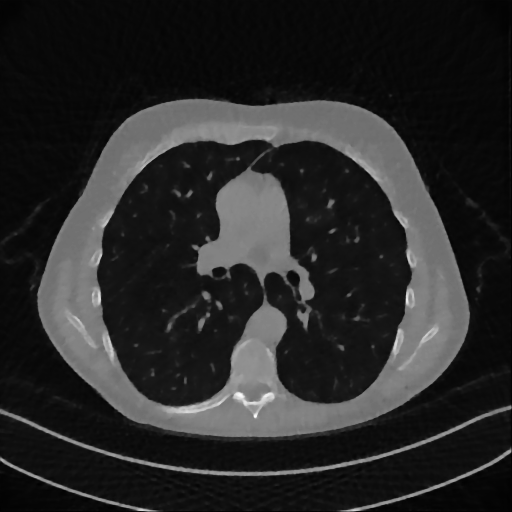

As visible from Figure 2, real full-dose medical images still present little noise and slightly visible streaking artifacts. This makes quite difficult to compute reliable metrics on the reconstructions. To fully exploit the full-reference image quality assessment metrics and validate our experiments, we create synthetic images and build few-view CT simulations, whose results are analysed in 5.2. In particular, the Constrasted Overlapping Uniform Lines and Ellipses (COULE) data set contains 430 sparse-gradient gray-scale images of 256×256256256256\times 256 resolution with many overlying objects, varying in size and contrast with respect to the background. The left image of Figure 3 shows one image of the data set as an example. The whole data set is downloadable from www.kaggle.com/loiboresearchgroup/coule-dataset.

Figure 3: From left to right: ground-truth and xISsubscript𝑥𝐼𝑆x_{IS} reconstruction of an image from the COULE data set.

The simulations are computed as before. We consider now different RIS images, i.e. xRIS=x(3)subscript𝑥𝑅𝐼𝑆superscript𝑥3x_{RIS}=x^{(3)}, xRIS=x(5)subscript𝑥𝑅𝐼𝑆superscript𝑥5x_{RIS}=x^{(5)} and xRIS=x(10)subscript𝑥𝑅𝐼𝑆superscript𝑥10x_{RIS}=x^{(10)} for the P360,360subscript𝑃360360P_{360,360} setting. We also explore different geometries P360,180subscript𝑃360180P_{360,180} and P360,60subscript𝑃36060P_{360,60}, by reducing the number acquired projections. On the right of Figure 3 we depict the SGP solution xISsubscript𝑥𝐼𝑆x_{IS} at convergence: we underline that it is visually not distinguishable from xGTsubscript𝑥𝐺𝑇x_{GT}.